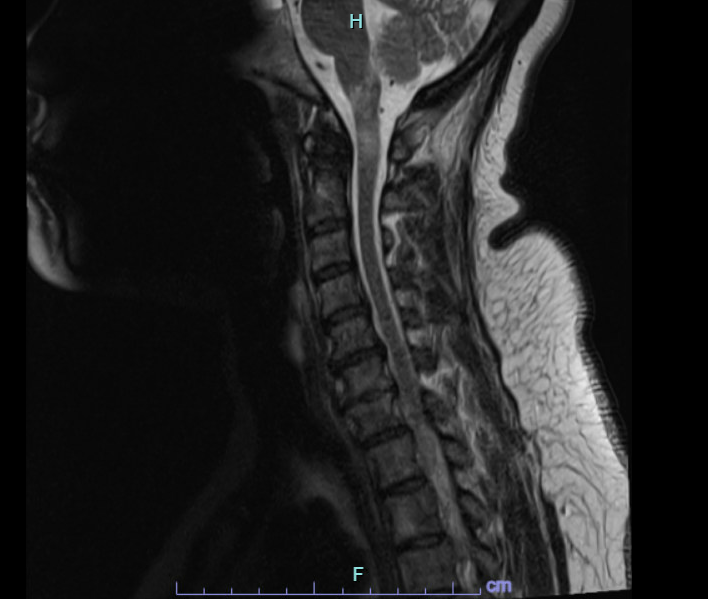

Case Presentation: A 47-year-old female with no significant past medical history presented to the emergency department in December with gastroparesis followed by progressive asymmetric weakness, numbness, and impaired gait associated with fall two years ago. MRI Brain was performed and unremarkable. She then developed a constant spinning sensation. She tried meclizine without benefit. The following month, she presented with numbness and tingling of the right hand that over the course of weeks spread to her left hand. She also described a “bandlike” thoracic sensation associated with upper/lower extremity weakness and balance impairment leading to fall. She was found to have an enhancing brainstem lesion on MRI brain performed on subsequent admission. MRI of the cervical/thoracic spine was consistent with demyelinating disease. She was treated with pulse IV Solu-medrol 500 mg BID for 3 days for central nervous system (CNS) demyelinating disease and then started on prednisone 80 mg daily. Myelin Oligodendrocyte Glycoprotein (MOG) antibody returned positive in serum. Also, found to have positive SSA/SSB without associated sicca or other clinical features. Given the constellation of recurrent short-segment myelitis, serum MOG antibody positivity and prominent therapeutic response to and dependence on steroids, the diagnosis of Myelin oligodendrocyte glycoprotein antibody-associated disorder (MOGAD) was made. Labs revealed negative Oligoclonal bands (OCB), anti-AQP4 neg, and + anti-MOG. IR-guided Lumbar puncture revealed: no white blood cells, few red blood cells, no xanthochromia, normal protein, and negative OCB. Borderline dsDNA noted. Patient is currently off steroids and receiving Rituximab-abbs (Truxima) infusions with neurology; other medications include Lacosamide and Cymbalta.